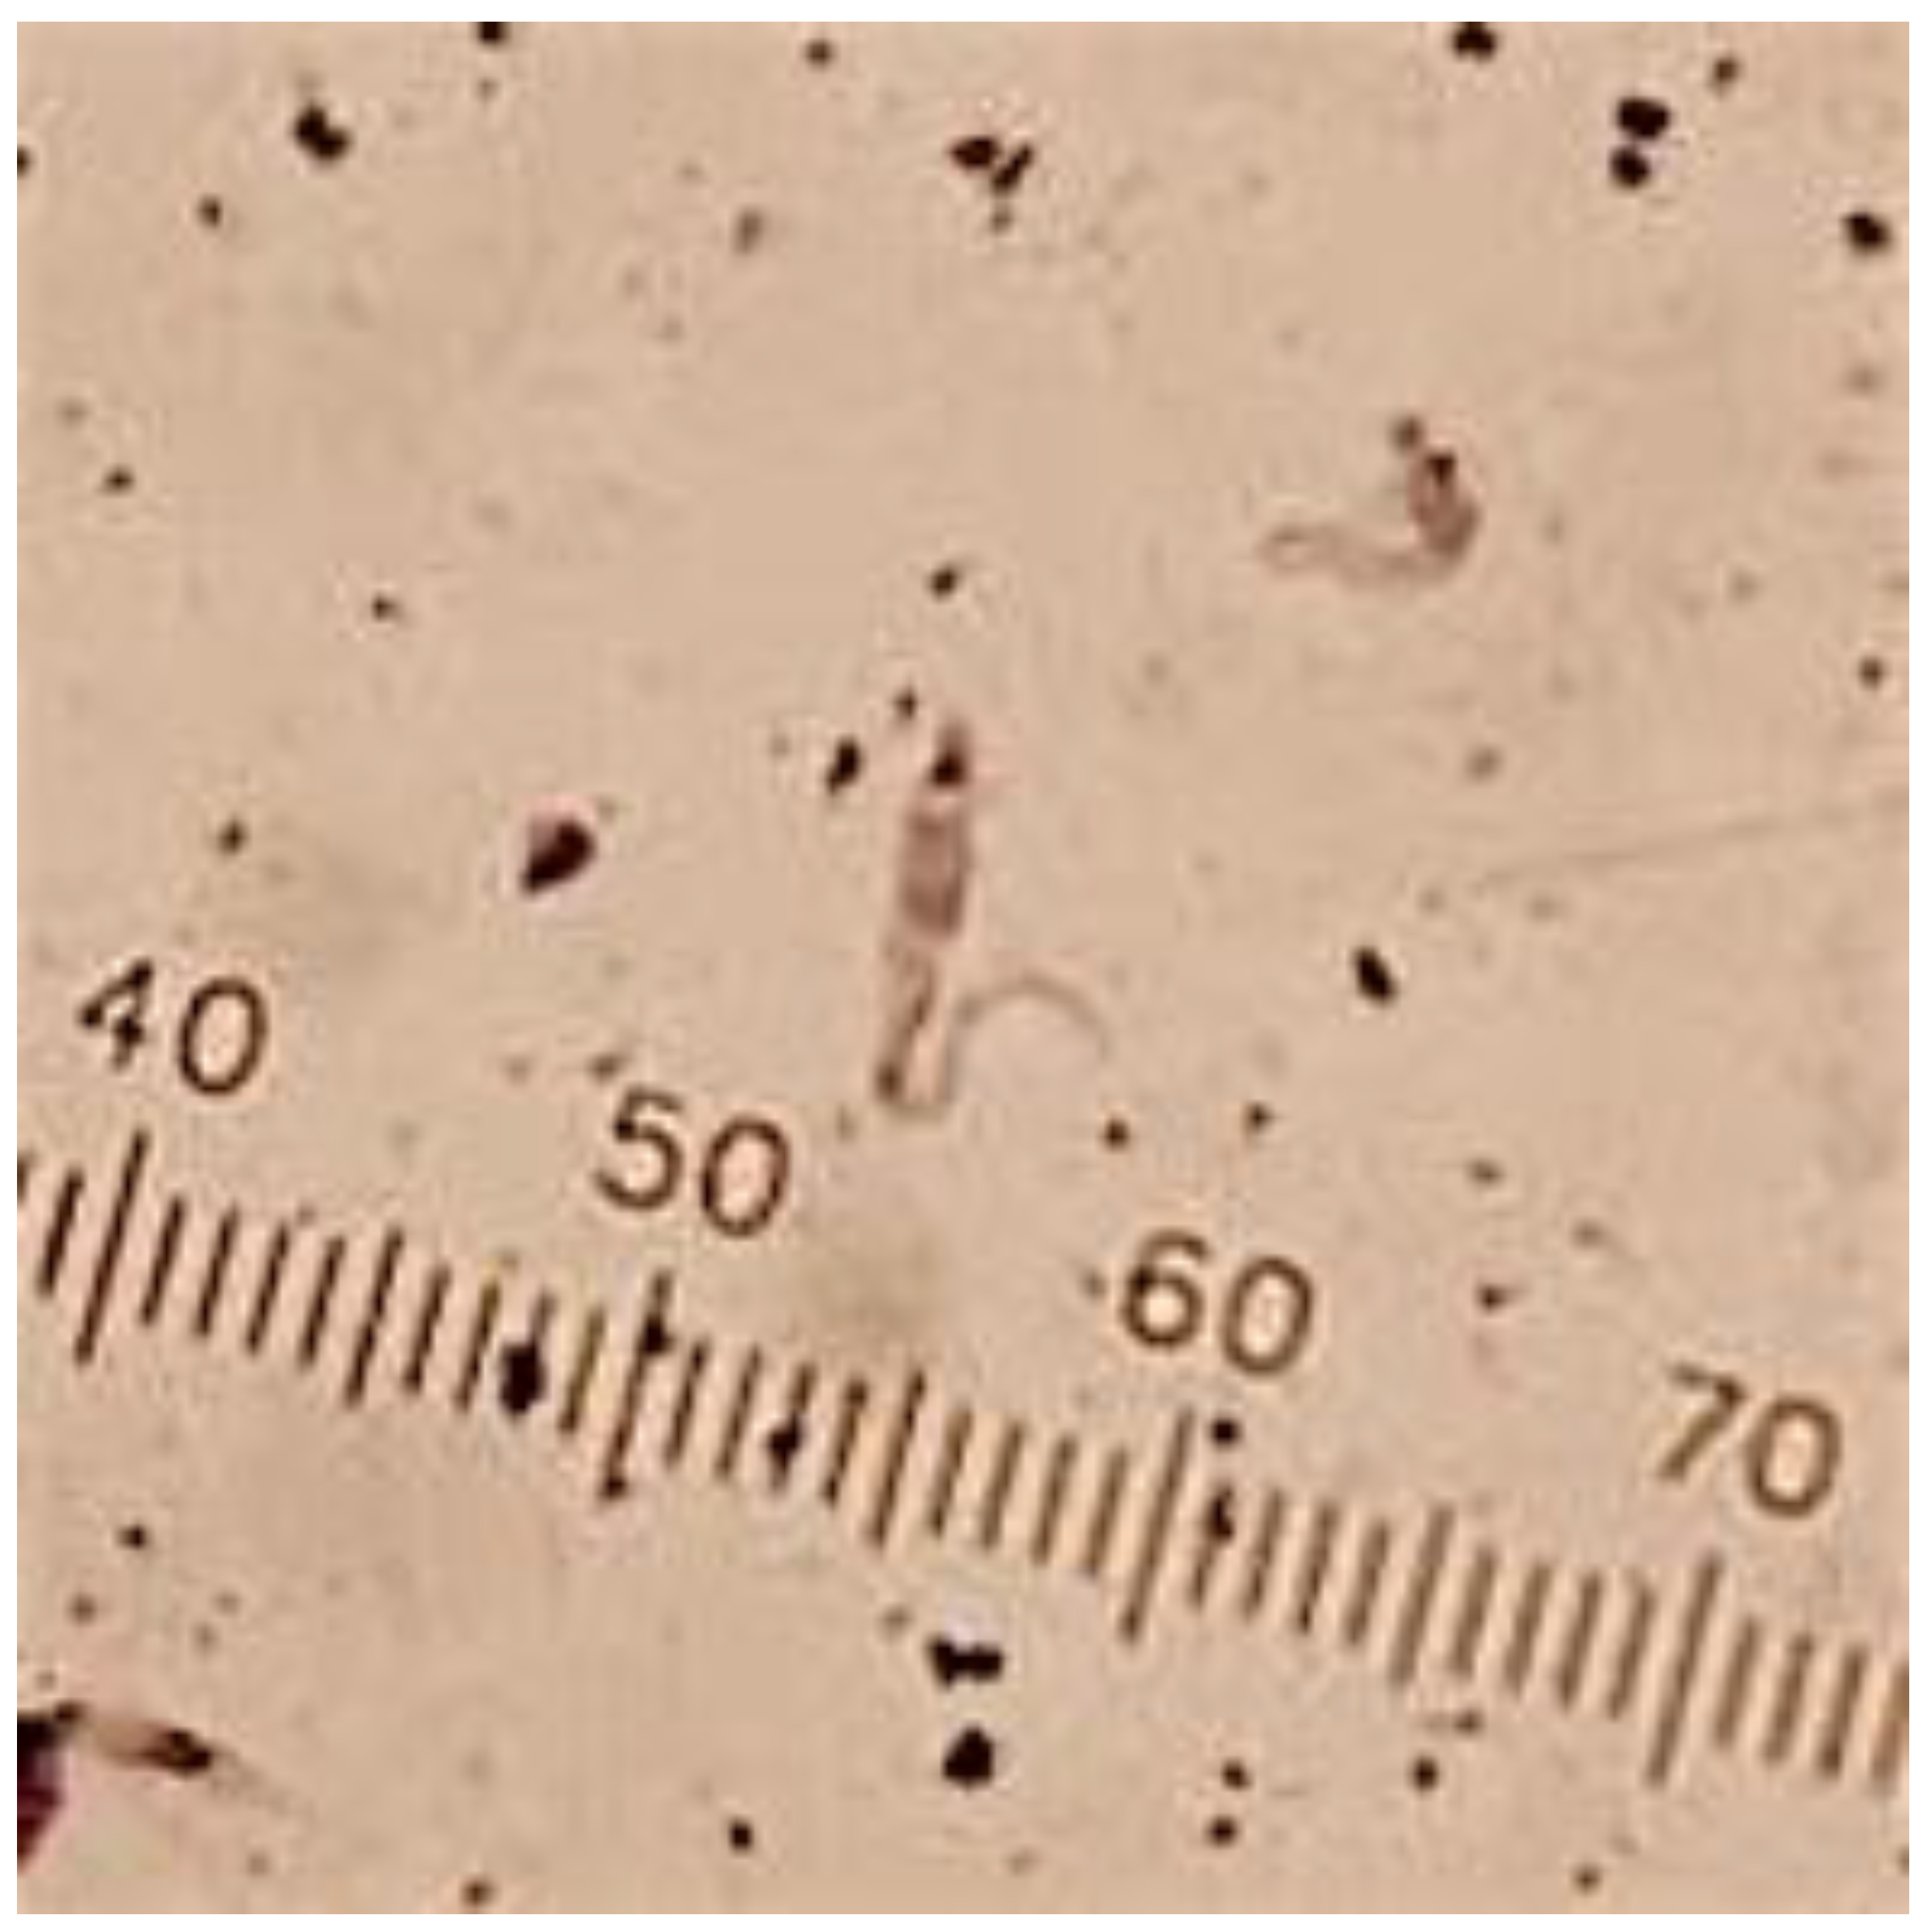

2.5. Specimen Processing and Molecular Analyses

3.1. T. cruzi Infection